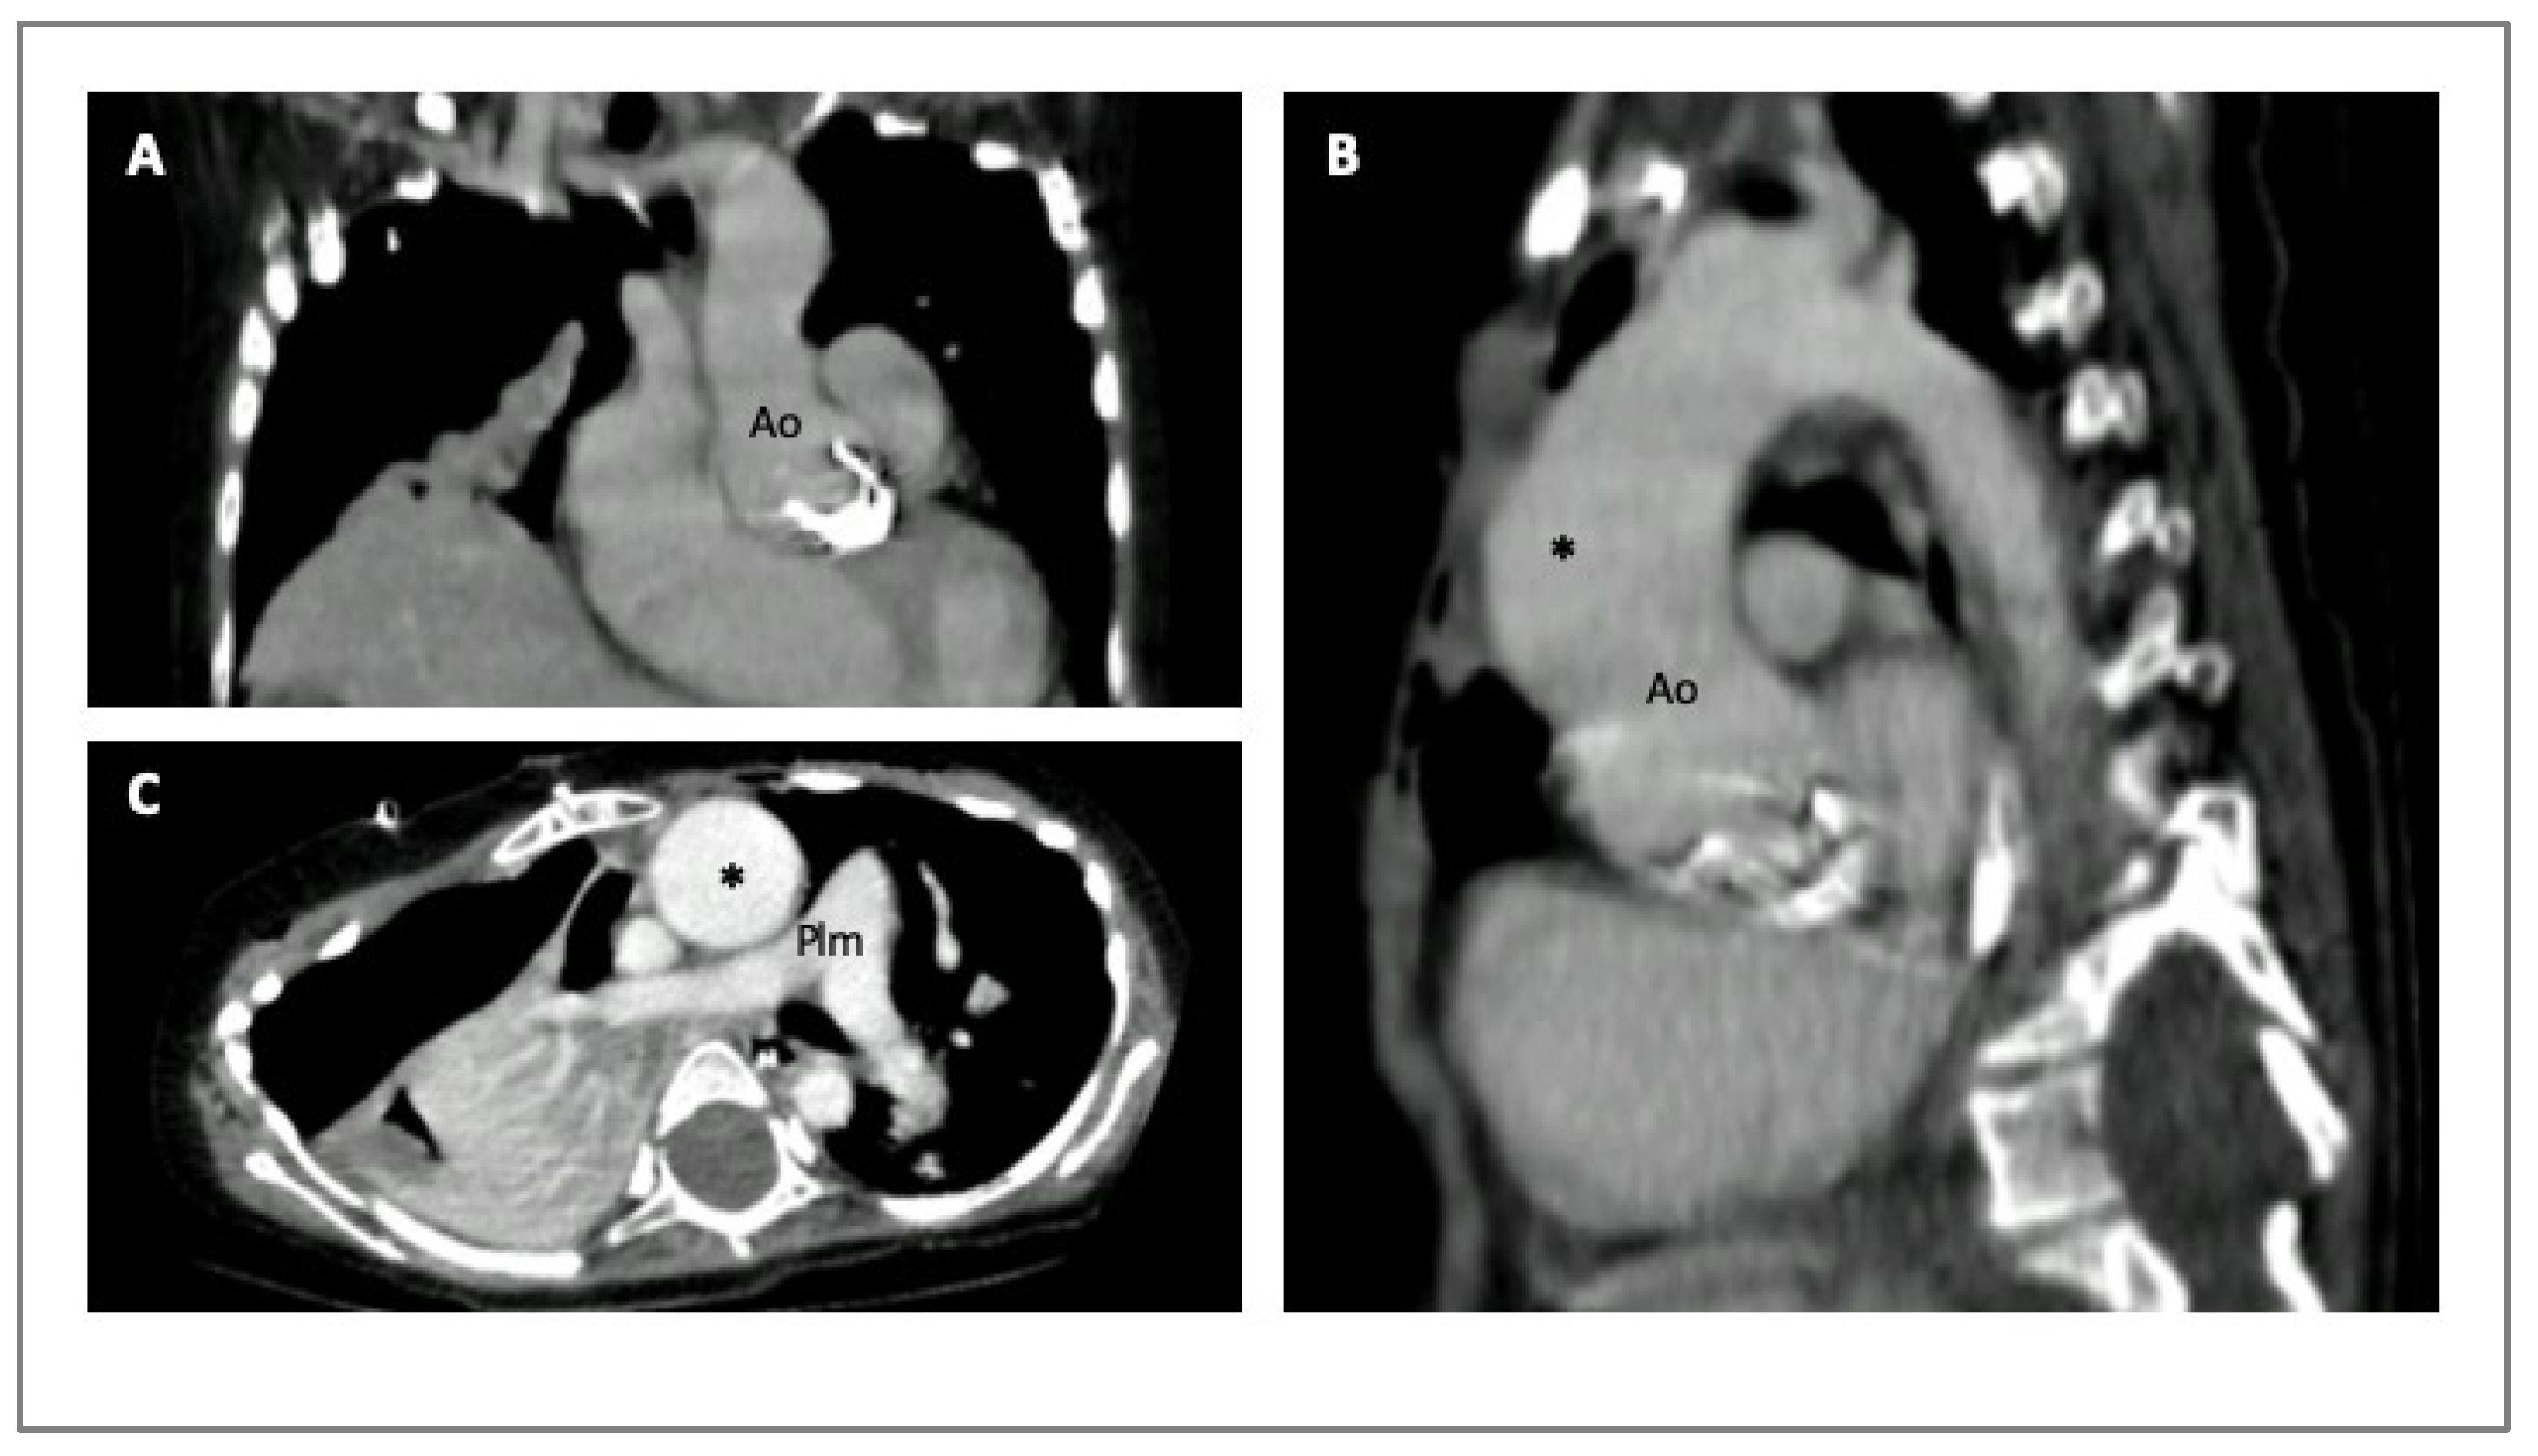

4. Imaging in HTADs

- Steinbrecher, K.L.; Marquis, K.M.; Braverman, A.C.; Ohman, J.W.; Bhalla, S.; Lin, C.Y.; Naeem, M.; Raptis, C.A. Imaging of Genetic Thoracic Aortopathy. Radiographics 2022, 42, 1283–1302. [Google Scholar] [CrossRef]